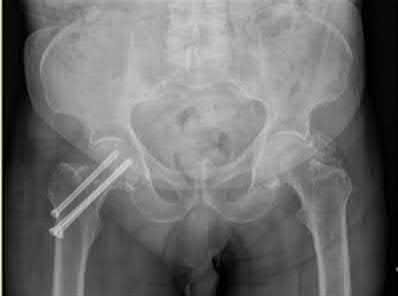

A 42-year-old male is brought to the trauma bay after a crush injury. Pelvic radiographs show widening of the pubic symphysis of 3.5 cm and disruption of the anterior sacroiliac ligaments, but intact posterior sacroiliac ligaments. According to the Young-Burgess classification, which type of pelvic ring injury does this represent?

Correct Answer: APC II

Explanation:

The Young-Burgess classification divides anteroposterior compression (APC) injuries into three types. APC I: symphysis widening <2.5 cm with intact SI ligaments. APC II: symphysis widening >2.5 cm with disruption of the anterior SI, sacrotuberous, and sacrospinous ligaments, but INTACT posterior SI ligaments (rotationally unstable, vertically stable). APC III involves complete disruption of anterior and posterior SI ligaments.